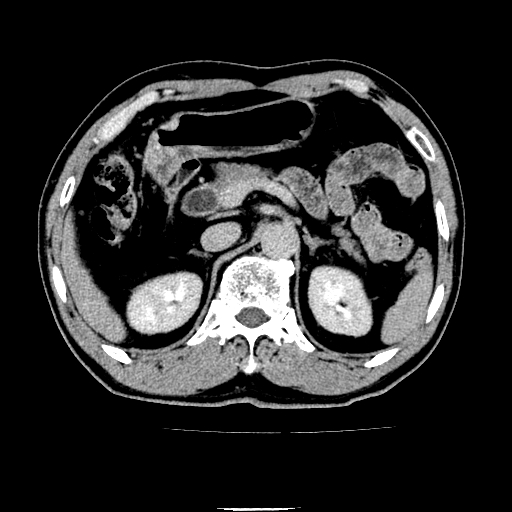

以下是引用chenqiong在2010-3-25 20:56:00的发言:[br]1、胆囊炎,胆囊息肉[br]2、肝内胆管及胆总管扩张,胆总管下端结石[br]3、十二指肠乳头旁憩室

以下是引用zxl51642在2010-3-26 10:47:00的发言:[br]胆囊炎,胆囊息肉,胆总管扩张,但未看到明显肿块,肝内胆管扩张不像恶性,炎性狭窄或阴性结石可能吧,建议mrcp,右肾小囊肿